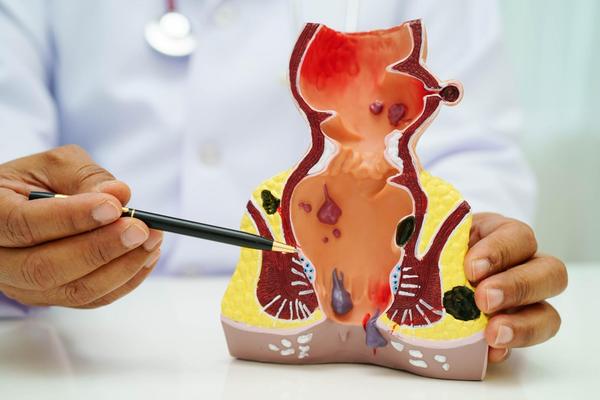

A hernia occurs when an internal organ pushes through a weak spot in the muscle, causing pain and swelling. At Dr Bharat Oza-Best General Laproscopy Surgeon PCMC in Punawale, hernia treatment is provided through advanced laparoscopic procedures.

Laparoscopic hernia surgery involves smaller incisions, which leads to less discomfort and a faster recovery compared to open surgery. This modern approach is highly effective for inguinal, umbilical, and incisional hernias, ensuring long-term relief and reduced risk of recurrence.

Patients benefit from shorter hospital stays, less scarring, and quicker return to normal activities. With precise techniques and experienced surgical care, hernia repair has become much safer and more reliable.